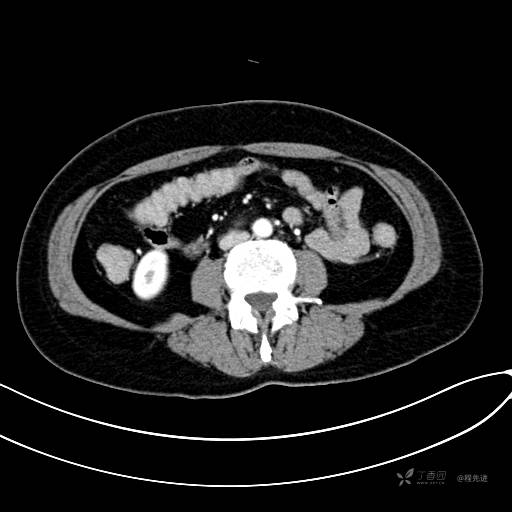

CT增强门脉期